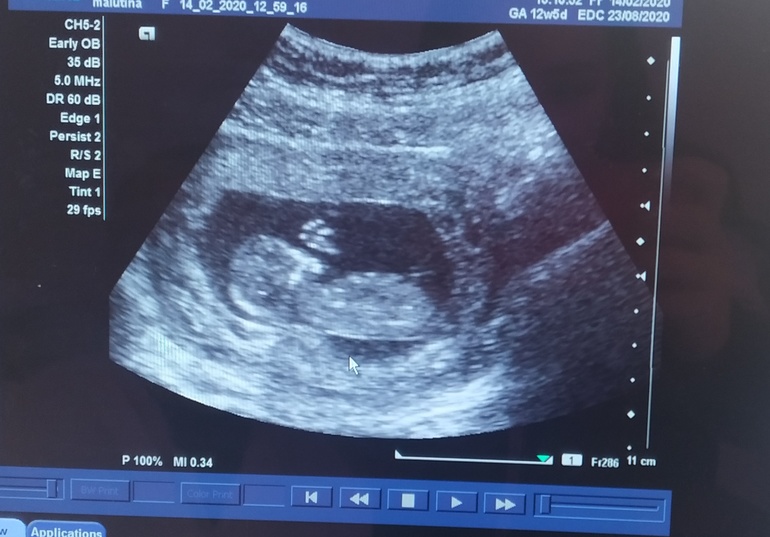

Первый скрининг и учёт

Сегодня 12+5

Ктр 64 мм

Нос 2.8 мм

Воротниковое пространство 2.1 мм